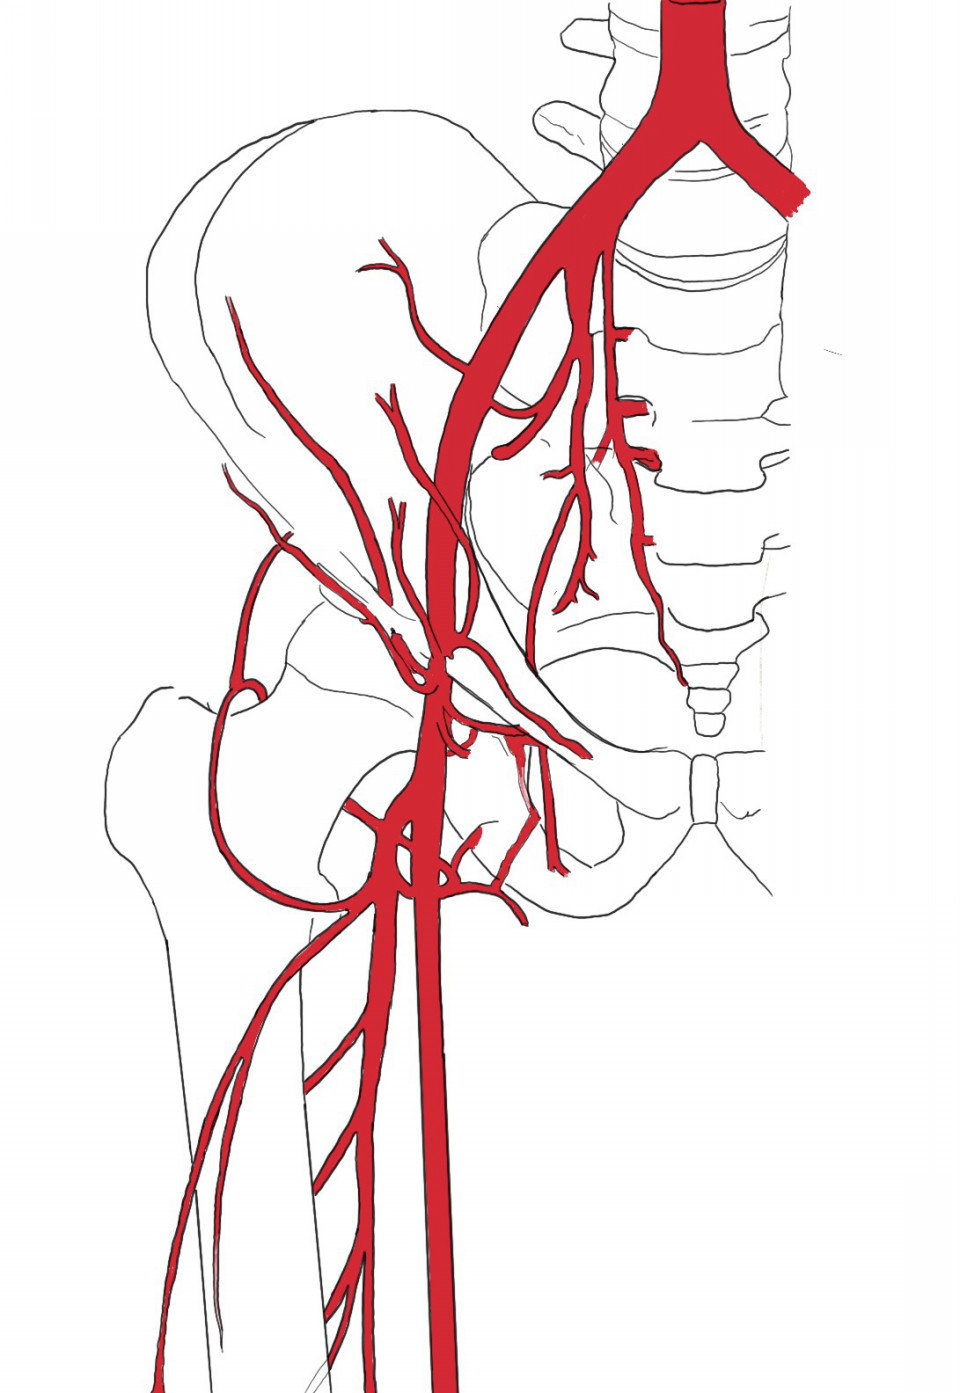

腹部外傷について

一般的に受傷機転と損傷を受けた構造の種類によって分類される

受傷機転

・鈍的

直接打撃、物体との衝突、または急な減速などがある

脾臓が最も損傷を受ける頻度が高い臓器であり、次いで肝臓および中空臓器(一般的には小腸)が多い

・穿通性

穿通性損傷は腹膜を穿通することも穿通しないこともある

また、穿通した場合に臓器損傷を引き起こさないこともある

刺傷は銃創よりも腹腔内の構造を損傷する可能性が低い

構造の種類

・腹壁

・実質臓器(肝臓、脾臓、膵臓、腎臓)

・中空臓器(胃、小腸、結腸、尿管、膀胱)

今回の症例は刺傷であり穿通性損傷となる

開腹手術にて動脈が3箇所傷あり止血処置